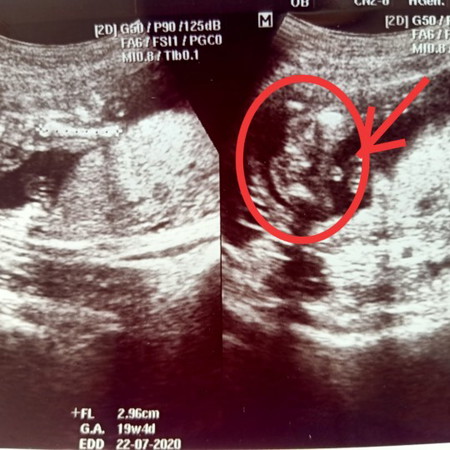

รบกวนแม่ๆ ช่วยดูเพศให้หน่อยค่ะ

แบบนี้เพศหญิง หรือชายค่ะ

จู๋โผล่มาแต่ใกล้เลยคะแม่